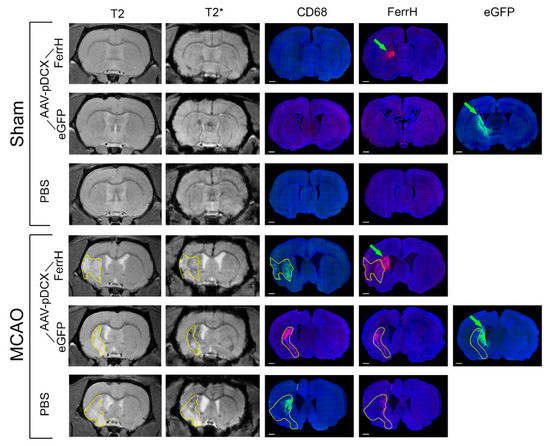

2.2. Injections of Both AAV-pDCX-FerrH and AAV-pDCX-eGFP Cause Signal Hypointensity on T2*-MGE Images in the Sham-Operated and Post-Ischemic Animals

2.3. T2* Signal Hypointensity Correlates with FerrH and eGFP Accumulation

- Results of our study showed that rat brain could be successfully infected with AAV-pDCX-FerrH and AAV-pDCX-eGFP viral vectors for expression of either ferritin or eGFP. Both vectors caused at about 20% decrease in signal hypointensity in the areas near the SVZ on T2*-weighted MRI at one month after intracranial injection of the viral constructs.

- The location of the signal hypointensity areas coincides with zones of ferritin and eGFP accumulation in immunohistochemical slides and zones of iron accumulation in Prussian blue staining a month after viral injection. RT-PCR data confirmed upregulated expression of the ferritin in the corpus callosum and caudoputamen in the left hemisphere of the rat brain on day 7 after intracerebral injected of the adenoviral vector construct.

- The main source of the signal hypointensity near SVZs in the AAV-pDCX-FerrH and AAV-pDCX-eGFP groups are mature neurons with a small percentage of young neurons.

- The main source of the signal hypointensity in the ischemic lesion area in AAV-pDCX-FerrH, AAV-pDCX-eGFP, and PBS-injected groups is macrophages.